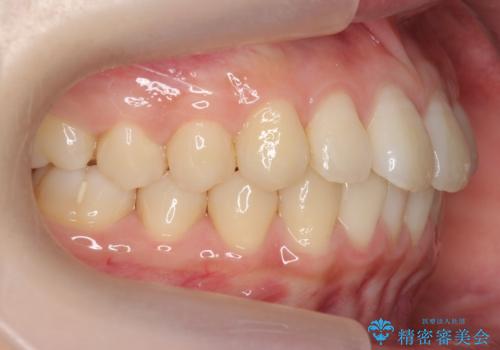

前歯のがたつき 部分矯正でコストダウンしながら、かみ合わせも治療

- 前歯のがたつきを気にして来院。

左下の小臼歯が捻転し、反対咬合になっていました。

先にワイヤーで部分矯正を行ってから、インビザラインの部分矯正を行いました。

先に難しい部分をワイヤー矯正することで、インビザラインの部分矯正コースで短期間で予算も抑えて確実に治すことができます。